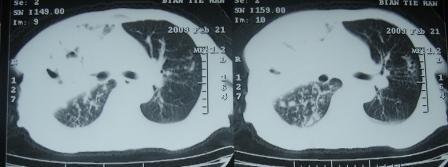

3月10号复查

考虑---干酪性肺炎并播散

右肺上叶干酪性肺炎并两肺支气管播散。

考虑---干酪性肺炎并播散。

考虑右肺上叶干酪性肺炎并支气管播散。

楼主  :谢谢大家发言  我和大家考虑的一样干酪性肺炎并播散